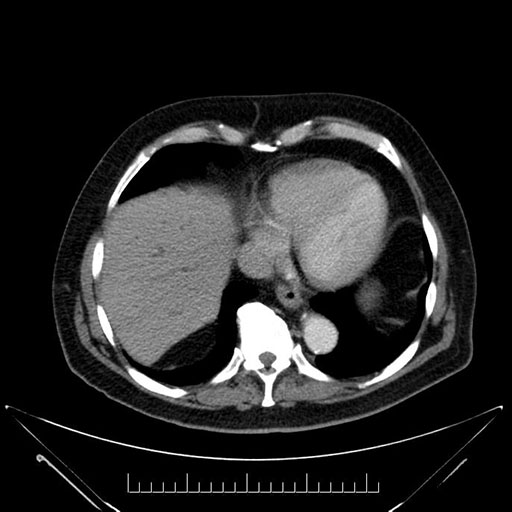

Whipple (pancreaticoduodenectomy) [case 7]

Imaging Analysis

Look through the patient's CT scan to identify any areas of concern for the necessary procedure.

Axial - stented